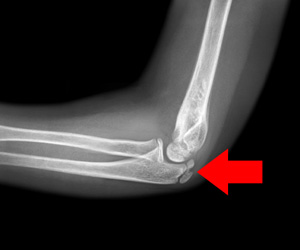

Elbow (Olecranon) Fractures

Olecranon fractures are described as a break in the bony tip of the elbow that sticks out when you bend your arm.

Distal Humerus Fractures of the Elbow

Injury in the distal humerus can cause impairment in the function of the elbow joint.

Radial Head Fractures of the Elbow

Radial head fractures are very common and occur in almost 20% of acute elbow injuries.